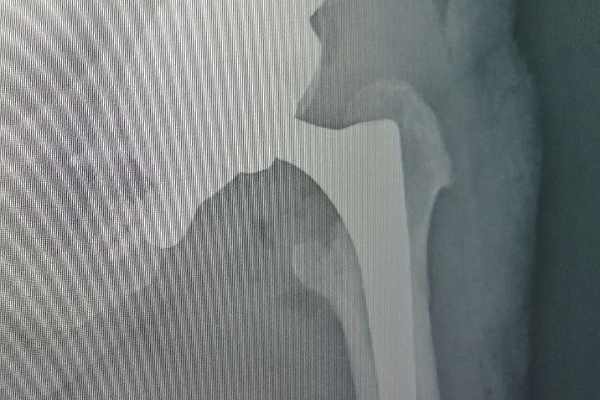

По КТ-снимкам 3D-принтер напечатал точную копию поврежденной тазовой кости. Затем был смоделирован фрагмент для замещения дефекта. Его выполнили в двух вариантах: из полимерного материала – для пробной примерки и из титана – для окончательной установки. Во время хирургического вмешательства 3D-эндопротез идеально встал на своё место. Заместив разрушенный участок кости титановым «двойником», травматологи-ортопеды смогли приступить к следующему этапу лечения – эндопротезированию всего тазобедренного сустава. Через сутки пациентка уже вставала на ноги с помощью дополнительной опоры, а сегодня под контролем инструкторов-методистов ЛФК разрабатывает новый сустав при ходьбе.